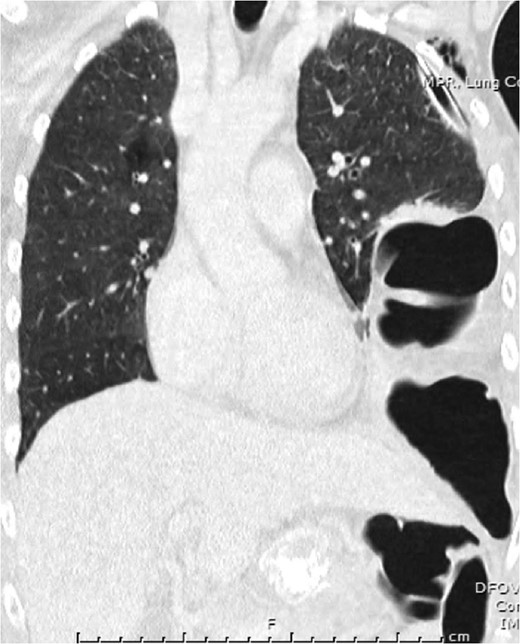

Representative coronal slice of computed tomography confirming the presence of a traumatic diaphragmatic hernia with a loop of incarcerated colon in the left hemithorax.